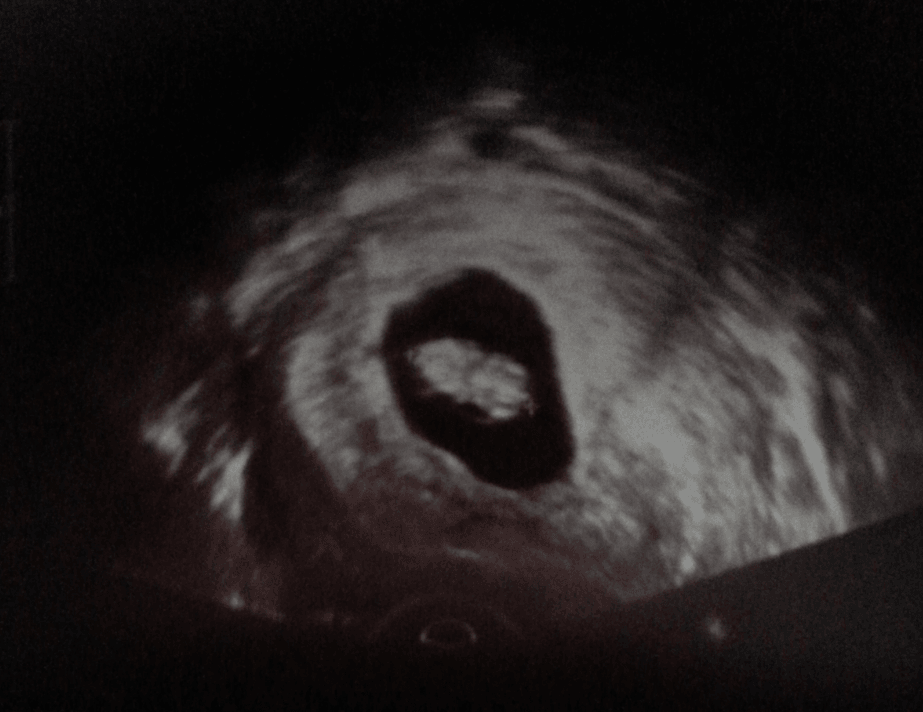

Hej dziewczyny;) Ja już jestem po wizycie u ginekologa. Jestem bardzo szczęśliwa. Z Dzidzią wszystko okej. Wiek ciążowy według OM to 9 tydzień i drugi dzień, i według usg też tak jest.

Pęcherzyk ciążowy GS-40mm

Dzidzia CRL-24 mm

Serce bije miarowo 163/min.

W załaczniku przesyłam wam foto mojej Fasolki ;)